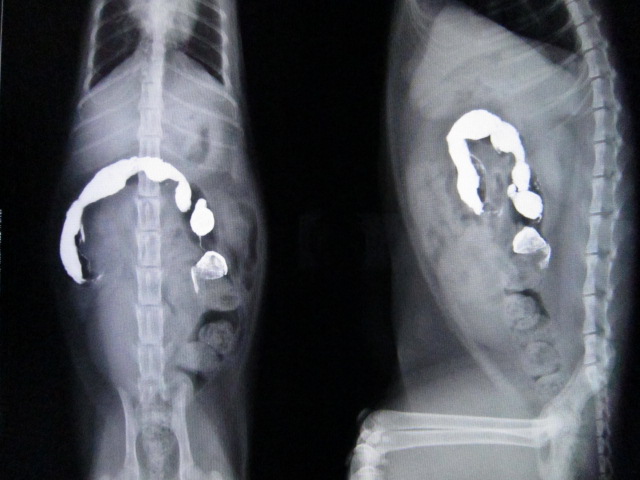

術後のレントゲンです。

異物はなくなりました。